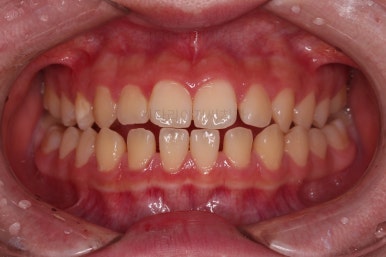

동래교정치과 초진 시 입안의 모습입니다.

치아가 벌어진 것도 벌어진 것이지만 교합이 전혀 안되고 있었어요.

틈새도 아랫니에 훨씬 많았고요.

윗니가 있는 위턱뼈가 전반적으로 아래턱에 비해 3차원으로 작은 양상이었습니다.

이번 환자분은 아랫니가 전반적으로 앞이든, 뒤든, 양옆으로든 넓어져 있는 양상이었고 그래서 아랫니에 틈도 많고 아래 앞니도 밀려나와 있는 양상인거죠.